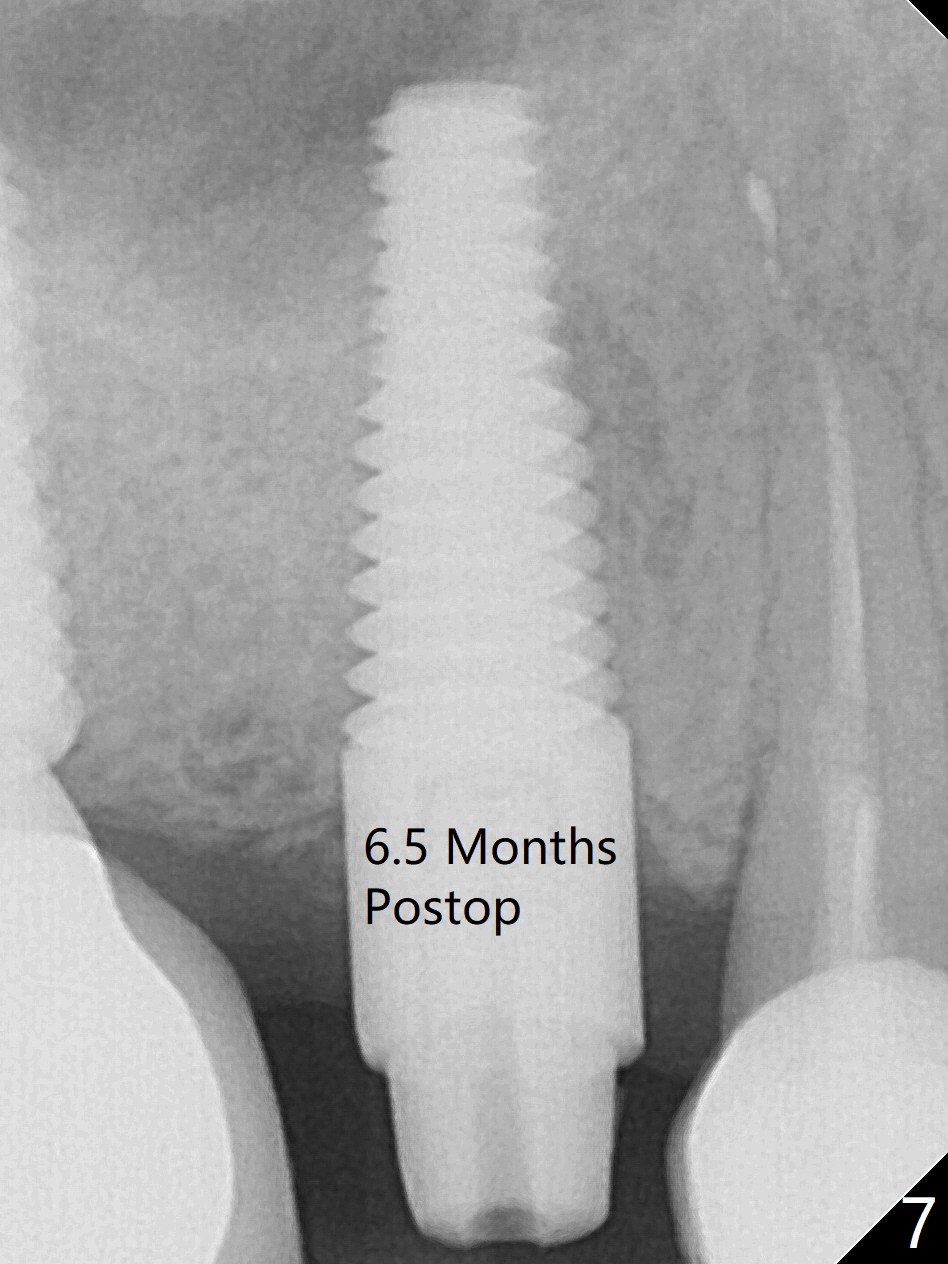

In spite of a fistula at #4, the buccal plate is present because of the exostosis (Fig.1 *). Since the socket is long and narrow, it is difficult to initiate osteotomy in the distal slope. Since the buccal plate is low, osteotomy is established as palatal as possible. The sinus floor is thin, but hard to elevate with Magic Sinus Lifter. Use of 3 mm Magic Expander leads to sinus floor break through and membrane perforation. After increase in the osteotomy with sequential expanders, a 5x20 mm tap is inserted with stability (Fig.2). Two pieces of PRF membrane are inserted for sinus membrane repair, followed by small amount of allograft (mixed with PRF, Fig.3 *) and a 4.5x17 mm dummy implant. A 5x17 mm tissue level implant is placed with >45 Ncm; with immediate placement of a 4x3 mm abutment (Fig.4), an immediate provisional is fabricated. There is no postop nasal hemorrhage. The immediate provisional has occlusal perforation 1.5 months postop. The tooth #13 has mobility due to its overuse and missing the teeth #14 and 18. Bitewing taken while redoing crown for #30 shows that the implant threads are subcrestal (Fig.5). There is no crestal bone resorption 6.5 months postop (Fig.6,7), while the periradicular radiolucency decreases (Fig.7).